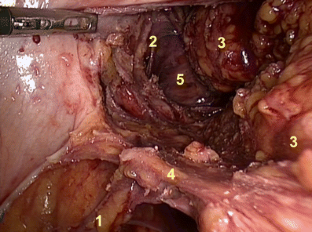

The key steps are: preparation of the splanchnic nerves at the mid-posterior sidewall, the hypogastric nerves at the upper sidewall, and the urogenital nerve branches (Walsh) at the caudal-anterior sidewall. The dissection of the lateral ligament is strictly performed as the last step. NOME was applied in 274 consecutive mesorectal excisions (partial 20.4 %, total 79.6 %); a subgroup of 42 male patients underwent a questionnaire-based interview on sexual activity.